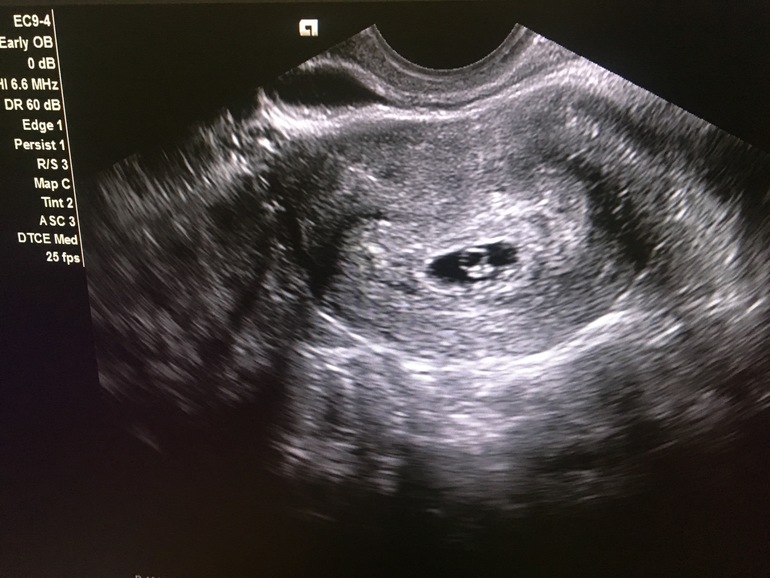

в 5.6 нед считая от 1 дня месячных нашли четко все. делала в Жк нашей , все показали на мониторе

вот 5.6 нед

14.10.2019